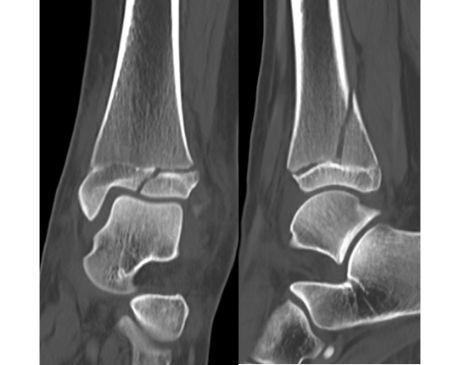

I was hit by car, had a compound fracture with a bone sticking out of my left foot. Broken tibia and fibia?. Screwed plate and bones back together. I am healing fine, next visit 3/26 to remove stiches. I seem to have total function of foot. Still have 2 more weeks of not using leg, but very hopeful.